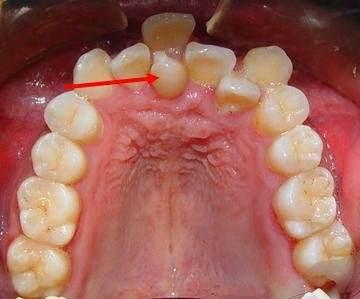

牙齒錯位并不僅僅是影響美觀的問題,而且還會帶來一些危害。

1、咬合功能受阻:出現牙錯位的患者會造成牙齒咬合功能受阻的情況,從而影響消化和吸收;

2、影響發音:牙齒錯位使患者口腔環境變得嚴峻,特殊的口腔環境甚至影響發音功能;

3、影響口腔衛生:因為牙錯位,牙齒會變得擁擠,則出現牙齒死角,導致患者在刷牙時很難徹底地清潔牙齒周圍,久而久之就會引發牙齒蛀牙病變。